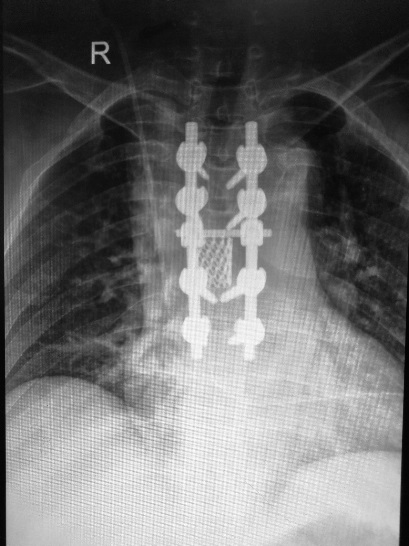

我院骨科在張富軍主任帶領(lǐng)下,李靖教授的指導(dǎo)下,分別于2017年9月1日和2017年9月29日順利為2位患者行全脊椎整塊切除手術(shù)。手術(shù)平均時(shí)間3個(gè)半小時(shí),手術(shù)過程順利,均按照術(shù)前計(jì)劃成功將椎體整塊切除,未出現(xiàn)手術(shù)并發(fā)癥,術(shù)后恢復(fù)良好。